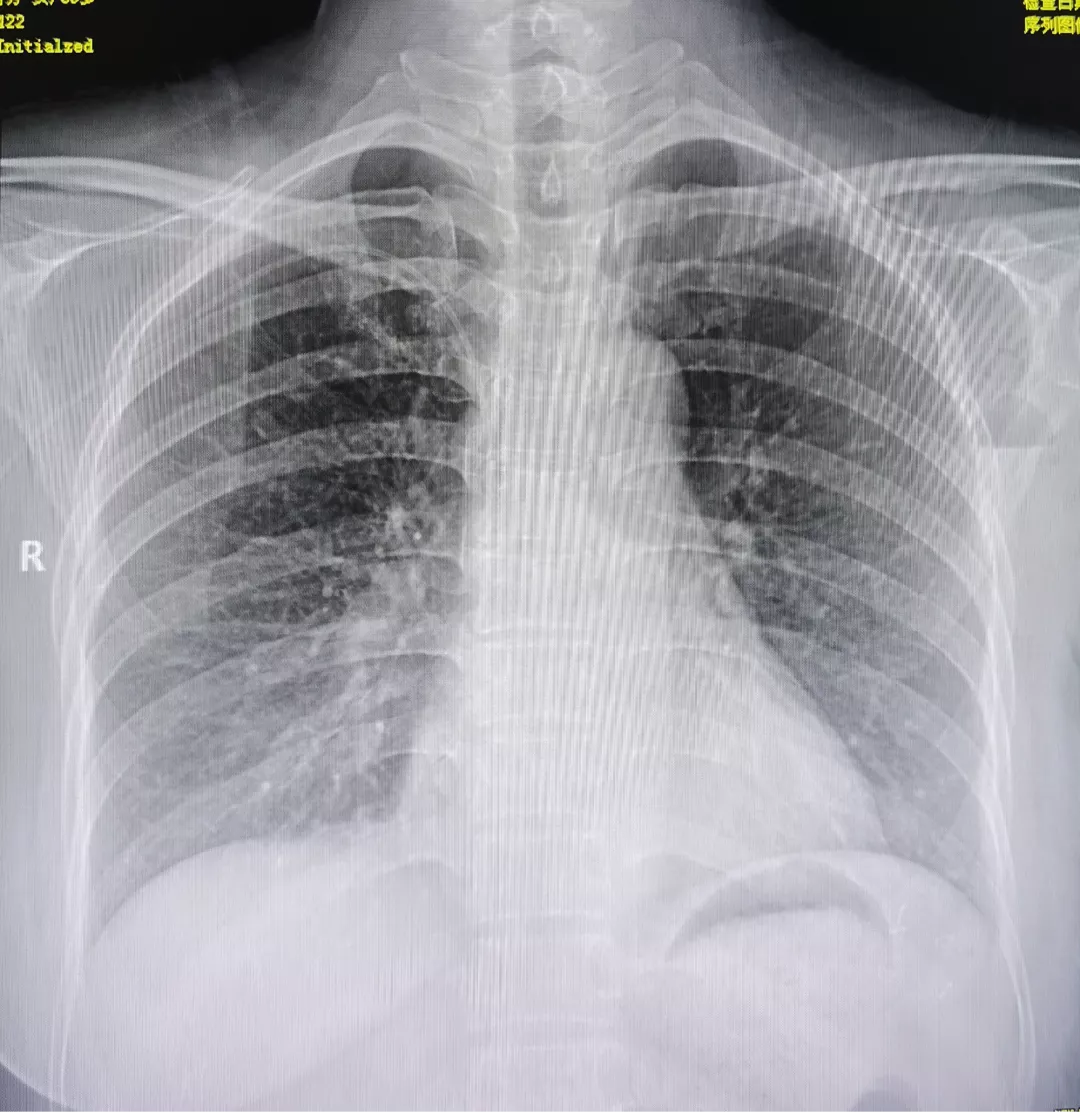

上午11时,在南昌市第三医院乳腺中心主任曹亚丽教授的指导下,由乳腺一科副主任刘秋明和PICC门诊副护士长邓勤通过医护合作的形式,完成南昌市第三医院首例手臂港植入术。手术顺利,整个操作过程20分钟,结合心电定位技术,为患者确定最佳的CAJ导管位置。

手臂港植入术为最新的静脉治疗技术,是在超声引导下置入上肢静脉导管,将输液港底座埋置于上臂内侧。目前,乳腺肿瘤患者接受化疗,一般选择PICC导管和胸壁输液港,而手臂输液港有更多优势,如下: